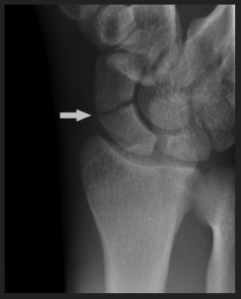

Cyriax était très systématique dans la prise en charge des douleurs de poignet après une chute. En effet, il savait que l’os scaphoïde fêlé pouvait se nécroser si le bras n’était pas plâtré de la main jusqu’au-dessus du coude. Les radiologues décrivaient déjà 6 incidences pour investiguer cet os, mais Cyriax avait constaté (à cause de la qualité des radios de l’époque) qu’on pouvait ne rien voir, « passer à côté ». Il avait donc émis une règle : « Toute suspicion de fissure du scaphoïde doit nous obliger à nous comporter comme s’il s’agissait d’une fracture (plâtre jusqu’au-dessus du coude) ».

Petite expérience personnelle : un patient vint me voir pour une « tendinite du poignet » traitée plusieurs semaines par physiothérapie sans résultat. Que disait-il ? « En livrant du mazout chez un client, j’ai eu un retour du tuyau sur mon poignet. Depuis j’ai très mal et je ne sais plus faire certains mouvements. La radio est négative. Il me semble que mon poignet est gonflé et que la douleur empire. J’ai mal la nuit. » Ce monsieur me consultait avec l’intuition qu’il ne s’agissait pas d’une tendinite… Il me disait : « Je crois que c’est plus grave que cela ».

– « J’ai eu un retour du tuyau » : il s’agit d’un traumatisme, donc (et malgré le diagnostic médical) une tendinite est peu probable.

– « Le repos, le traitement et la gymnastique chez le kiné ne m’aident pas » : le diagnostic est peut-être à revoir.

– « Mon poignet est un peu gonflé et certains mouvements empirent la douleur » : quels mouvements ? qu’en est-il si on les reproduit passivement ?

Conclusion temporaire :

Ce n’est sans doute pas une tendinite (d’autant que les tests tendineux ne reproduisent pas la douleur et que les tendinites ne sont pas causées par un traumatisme).

Cela pourrait être osseux (gonflement du poignet, choc du tuyau, douleur la nuit)

Mais la radio est négative…

Quand a-t-elle été réalisée ?

Réponse : le lendemain du traumatisme.

Or les fissures ne se voient parfois qu’après plusieurs jours…

Donc : radios à refaire (selon les six incidences classiques).

Résultats : pas de fracture, pas de fissure.

Le patient dit toujours la même chose et l’examen du poignet fait penser à une fissure du scaphoïde…

Croire le patient.

Qu’aurait fait Cyriax ? Suspicion de fissure du scaphoïde = on se comporte comme s’il y avait une fracture = plâtre jusqu’au-dessus du coude.

Mais cela ne fut pas fait, le patient continuait à souffrir et les semaines passaient…

À l’époque de Cyriax, la scintigraphie n’existait pas.

J’insistai pour obtenir une scintigraphie.

(La scintigraphie permet de visualiser l’activité de l’os -augmentée en cas de fissure ou de fracture par exemple.)

Résultats : fissure ou fracture du scaphoïde.

Malheureusement, ce patient n’a pas été plâtré jusqu’au coude = nécrose du scaphoïde = opération = deux ans d’arrêt de travail !